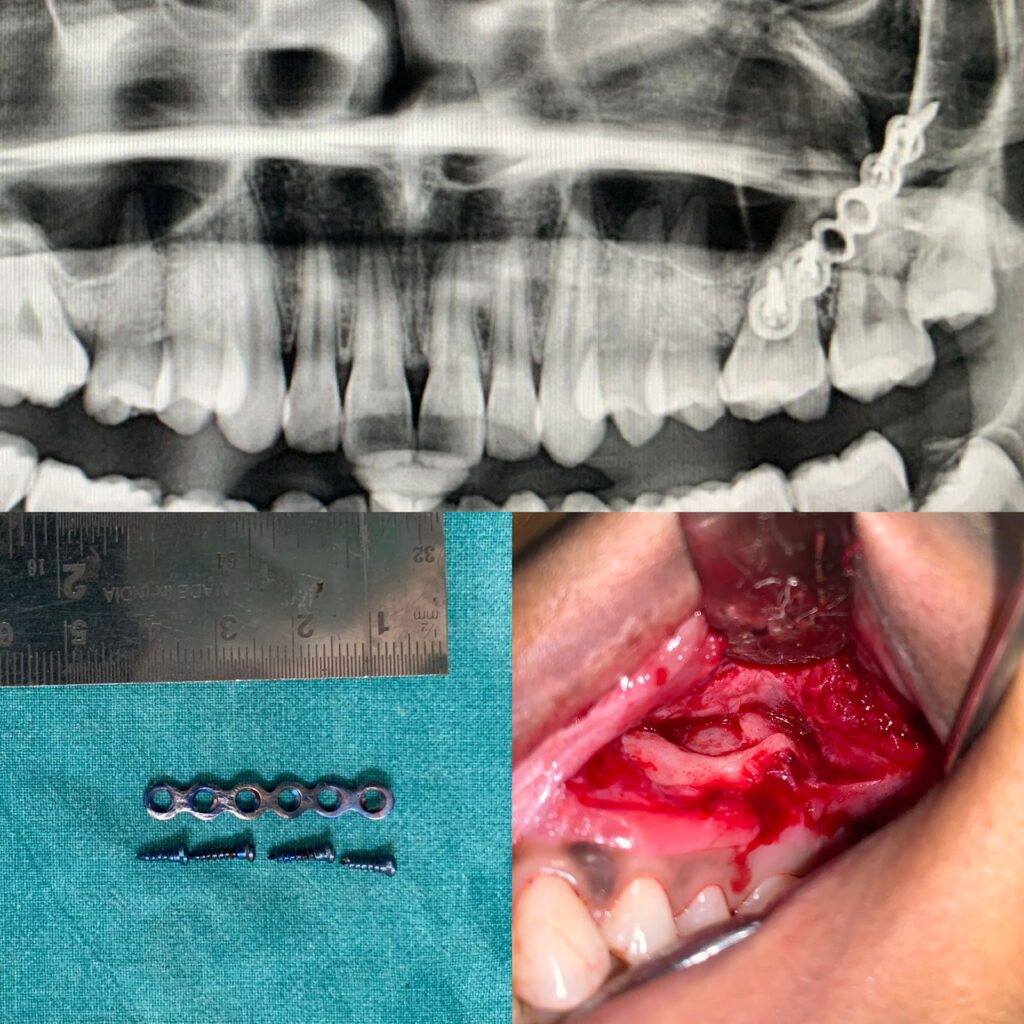

Case of plate removal from the ZMC region.